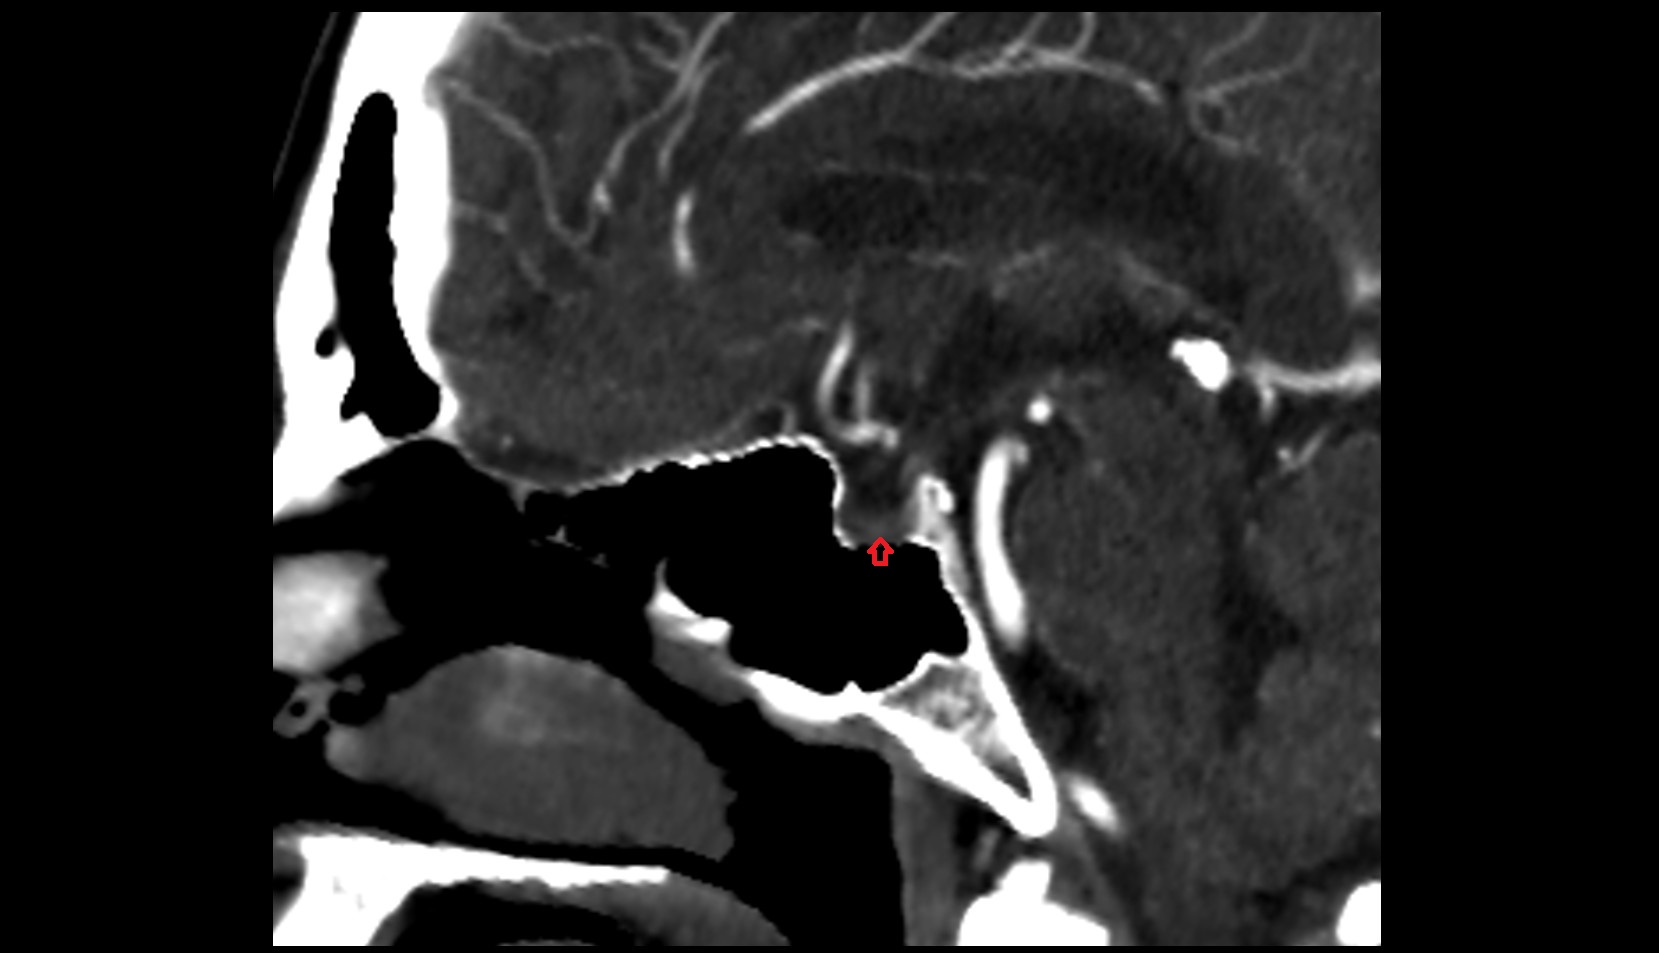

- Uterus

- Body of uterus

- Fundus of uterus

- Cervix of uterus

- Isthmus of uterus

- Vagina

- Endocervical canal

- Stroma of the cervix

- Internal os of the cervix

- External os of the cervix